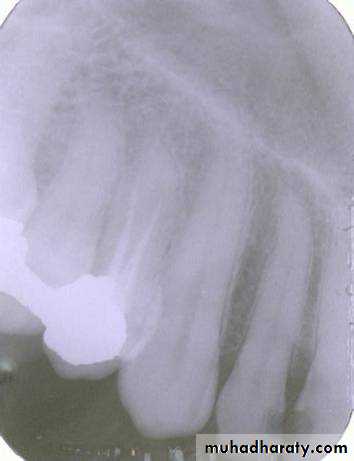

FISSURE BUR

FOREIGN BODY